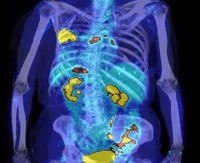

ПЭТ-КТ всего тела. Это радионуклидный томографический метод диагностики, который используется для одноразового и детального обследования всего организма. Позитронно-эмиссионная томография позволяет изучать распределение и накопление предварительно введенных радиофармацевтических препаратов (ЗП) во внутренних органах и тканях. С развитием злокачественных новообразований, метастазов, воспалительных или дистрофических патологий изменяется активность химических процессов, что проявляется изменением цветовой гаммы на полученных изображениях. В настоящее время для прохождения ПЭТ радиопрепараты вводятся исключительно внутривенным путем, и их наиболее распространенными представителями являются 18F-фтордезоксиглюкоза, 11C-метионин и 11C-тирозин.

ПЭТ-КТ позволяет изучать активность метаболических процессов органов и тканей путем оценки количества радиофармпрепаратов в коленном суставе. Однако чем выше скорость обмена веществ в организме, тем больше радиофармпрепаратов накапливается в нем. Для всех анатомических структур в нормальном состоянии характерна определенная скорость химических реакций, которая отображается соответствующим цветом на томограмме. Для упрощения анализа изображения и стандартизации данных, полученных с помощью ПЭТ, используется сравнительная эталонная шкала интенсивности накопления RFP - шкала внедорожника. По ее словам, степень нормального накопления радиофармпрепаратов в тканях всего организма можно разделить на 4 уровня:

• Я - реагирует на мягкие ткани и мышцы в расслабленном состоянии, в которых практически не накапливаются радиофармацевтические препараты. На томограмме отображается менее яркие цвета - серый, темно-синий.

• II - соответствует печени и другим внутренним органам. Они имеют относительно низкую скорость метаболизма и визуализируются в оттенках зеленого.

• III - промежуточный уровень активности химических процессов «между печенью и мозгом». Чаще всего он характеризуется диапазоном цветов от желтого до красного.

• IV: характеризует мозг. Самый высокий уровень метаболической активности среди всех нормальных тканей организма. На ПЭТ он отображается красным или белым.

В зависимости от характеристик сканера и его настроек эти цвета могут отличаться. Аномальное повышение метаболической активности в конкретном органе является симптомом патологических нарушений. Исходя из параметров шкалы внедорожника, можно не только диагностировать заболевание до развития структурных изменений, но и оценить его характер.

• Уровень активности II накопления радиофармпрепаратов по шкале внедорожника соответствует воспалительным изменениям в этой области.

• Уровень III является признаком опухоли или метастазирования, редко хронического воспаления.

• Накопление радиофармацевтических препаратов уровня IV за пределами ткани головного мозга указывает на первичную опухоль или метастатическое поражение.

Соответственно, низкая биохимическая активность в органах, которые не характерны для них, свидетельствует о ишемических и дегенеративных изменениях. По шкале SUV снижение уровня накопления радиофармпрепаратов в различных анатомических структурах может указывать на наличие ишемической болезни сердца, инфаркта миокарда, рассеянного склероза, болезни Альцгеймера и других заболеваний.